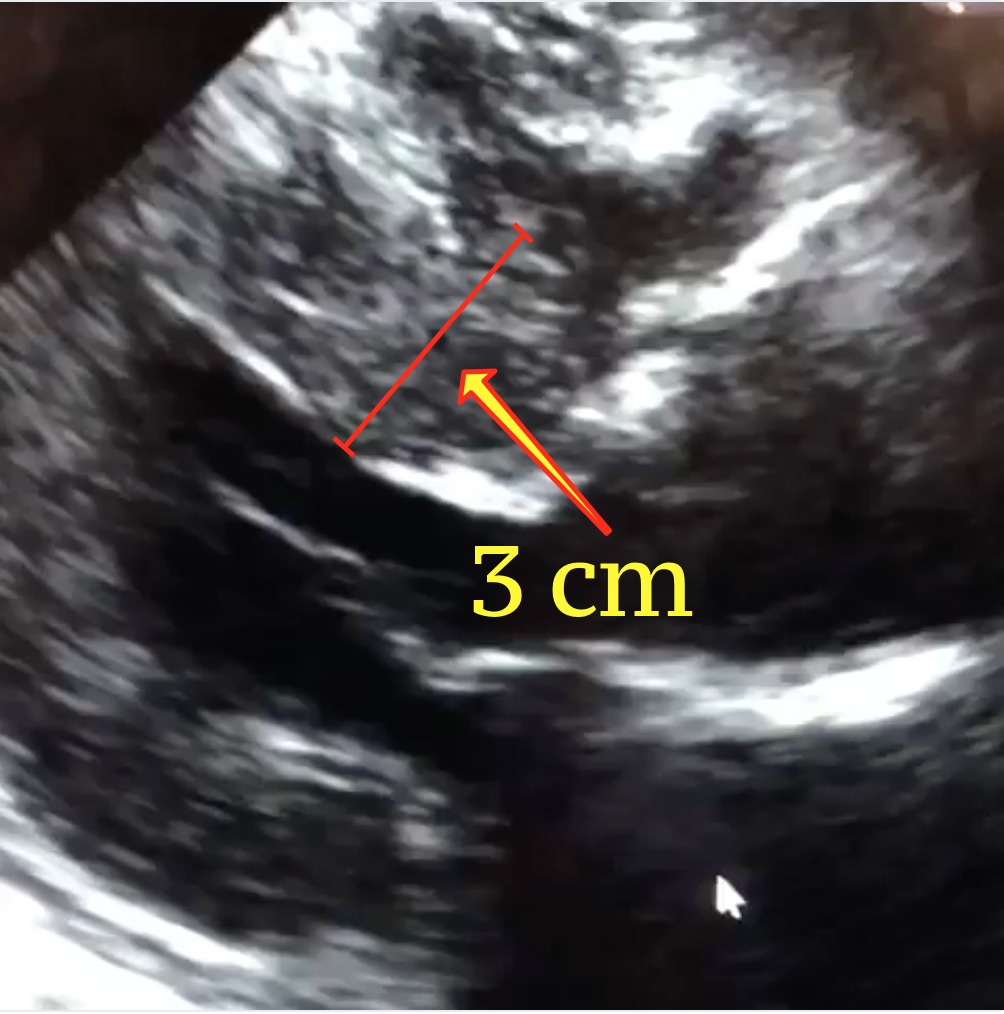

La ecocardiografía es la prueba por excelencia para diagnosticar la cardiomiopatía hipertrófica. El eco puede identificar dónde está el músculo engrasado, medirlo y cuantificar el efecto que este podría estar teniendo sobre el flujo de sangre. Es común que el electrocardiograma de un paciente con MCH salga anormal; esto puede ayudar a entender mejor la condición. El ECG es otra herramienta de detección excelente para HCM. Cuando usted ve a una cardióloga por primera vez, es por eso que se le manda un Eco preliminar. En los últimos años, el MRI cardiaco ha surgido como una de las herramientas más importantes de la proyección de imágenes para el corazón gracias a su capacidad para producir imágenes muy detalladas. Un MRI cardiaco puede ayudar a diagnosticar la MCH con mucha precisión. Puede detectar incluso pequeñas cantidades de músculo grueso que podrían no ser detectadas en la ecocardiografía.